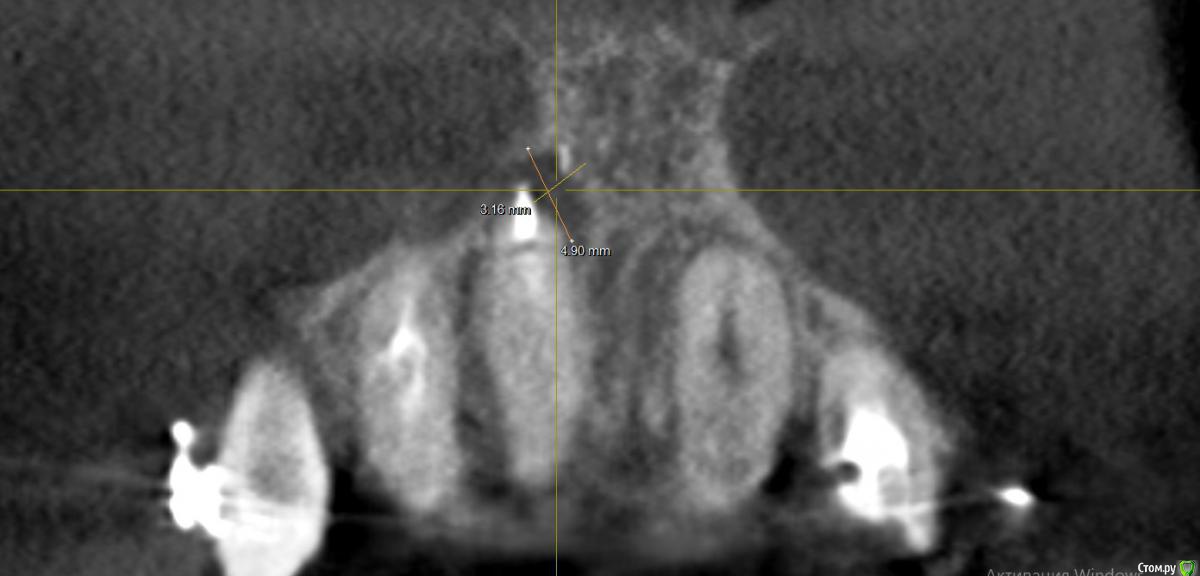

Al..ks Опубликовано 18 апреля, 2019 Поделиться Опубликовано 18 апреля, 2019 Добрый день. Планируется имплантация(15 или 14. брекеты ношу, поэтому не знаю какой будет)+аугментация (в области кармана 17 и при имплантации в случае недостатка кости)+пластика десны+установка формирователя. Все за раз.На выбор dentium, Astra, Nobel, Straumann. Подходят любые и выбор за мной(я склоняюсь к Астре). Правильный выбор? . Плюс ко всему по КТ там отсутствует кортикальный слой( по словам врача) я так понял с наружней стороны, поможет ли аугментация?И поможет ли она с карманом 17? И так как двигали зубы в области корня 11 появилась пустота (толи уже было)в середине лечения и на данный момент Надо ли делать резекцию корня - или канал перелечивать (там ставили СВШ перед брекетами) перед протезирование? Ссылка на комментарий

suballex Опубликовано 19 апреля, 2019 Поделиться Опубликовано 19 апреля, 2019 Добрый день. Планируется имплантация(15 или 14. брекеты ношу, поэтому не знаю какой будет)+аугментация (в области кармана 17 и при имплантации в случае недостатка кости)+пластика десны+установка формирователя. Все за раз.На выбор dentium, Astra, Nobel, Straumann. Подходят любые и выбор за мной(я склоняюсь к Астре). Правильный выбор?Правильный Плюс ко всему по КТ там отсутствует кортикальный слой( по словам врача) я так понял с наружней стороны, поможет ли аугментация?И поможет ли она с карманом 17?Аугментация с карманом не поможет. В остальном - да И так как двигали зубы в области корня 11 появилась пустота (толи уже было)в середине леченияи на данный момент Надо ли делать резекцию корня - или канал перелечивать (там ставили СВШ перед брекетами) перед протезирование?Нужно сравнить КТ начала лечения и последнее. Рентгенологически, канал 11 пролечен хорошо. Возможно, это остаточные явления. Ссылка на комментарий